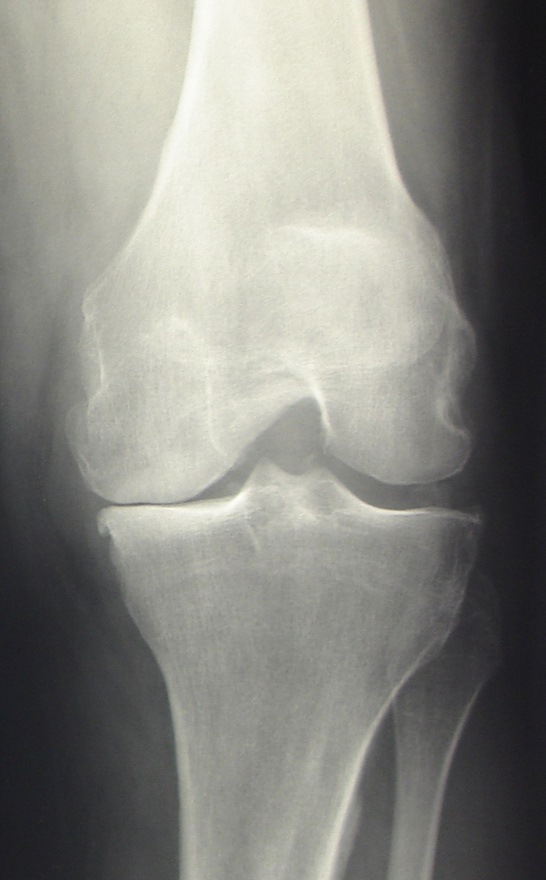

fortgeschrittene Arthrose des Kniegelenkes

Bei der Kniegelenksarthrose wird die verschlissene Knorpeloberfläche der Gelenkpartner durch eine Metalloberfläche ersetzt („Oberflächenersatz“). Dabei wird auf den in mehreren Ebenen exakt zugesägten Oberschenkelknochen eine Metallkappe aufgeschlagen, am Unterschenkel eine dünne Scheibe mit dem verschlissenen Knorpel entfernt und mit einer Metallplatte versehen. Als Gleitschicht zwischen beiden Komponenten dient ein sog. Inlay aus Polyethylen.